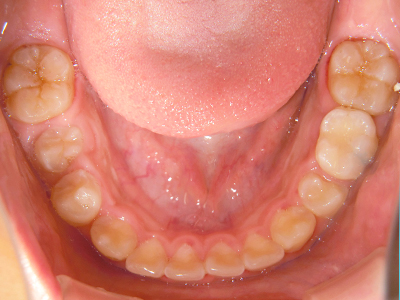

【4】矯正治療

矯正装置を装着し、調整しながら少しずつ歯を移動させ、歯並びを整えていきます。

【5】保定期間

治療後の一定期間は、定期的にチェックを行い経過観察していきます。